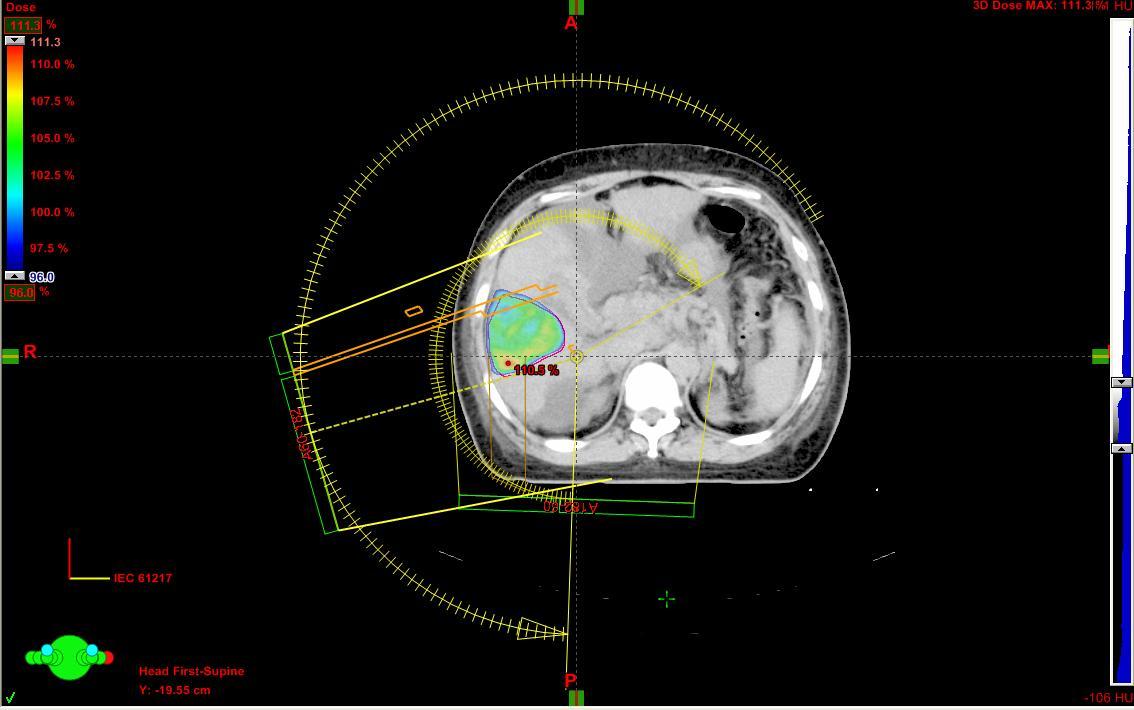

圖二: 全身立體定位放射治療(SBRT/SABR)之橫切面劑量分布圖